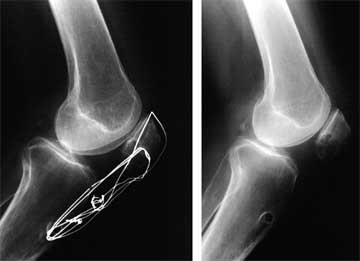

The left hand x-ray is of a patient’s knee before an anterior cruciate ligament reconstruction and meniscus repair that were performed at another orthopaedic Center. The patella is in the normal position. The right x-ray is of the same knee just 4 weeks following surgery after the patient was referred to our Center with significant quadriceps atrophy and limited knee motion and patellar mobility. You can see that the patella has dropped significantly.